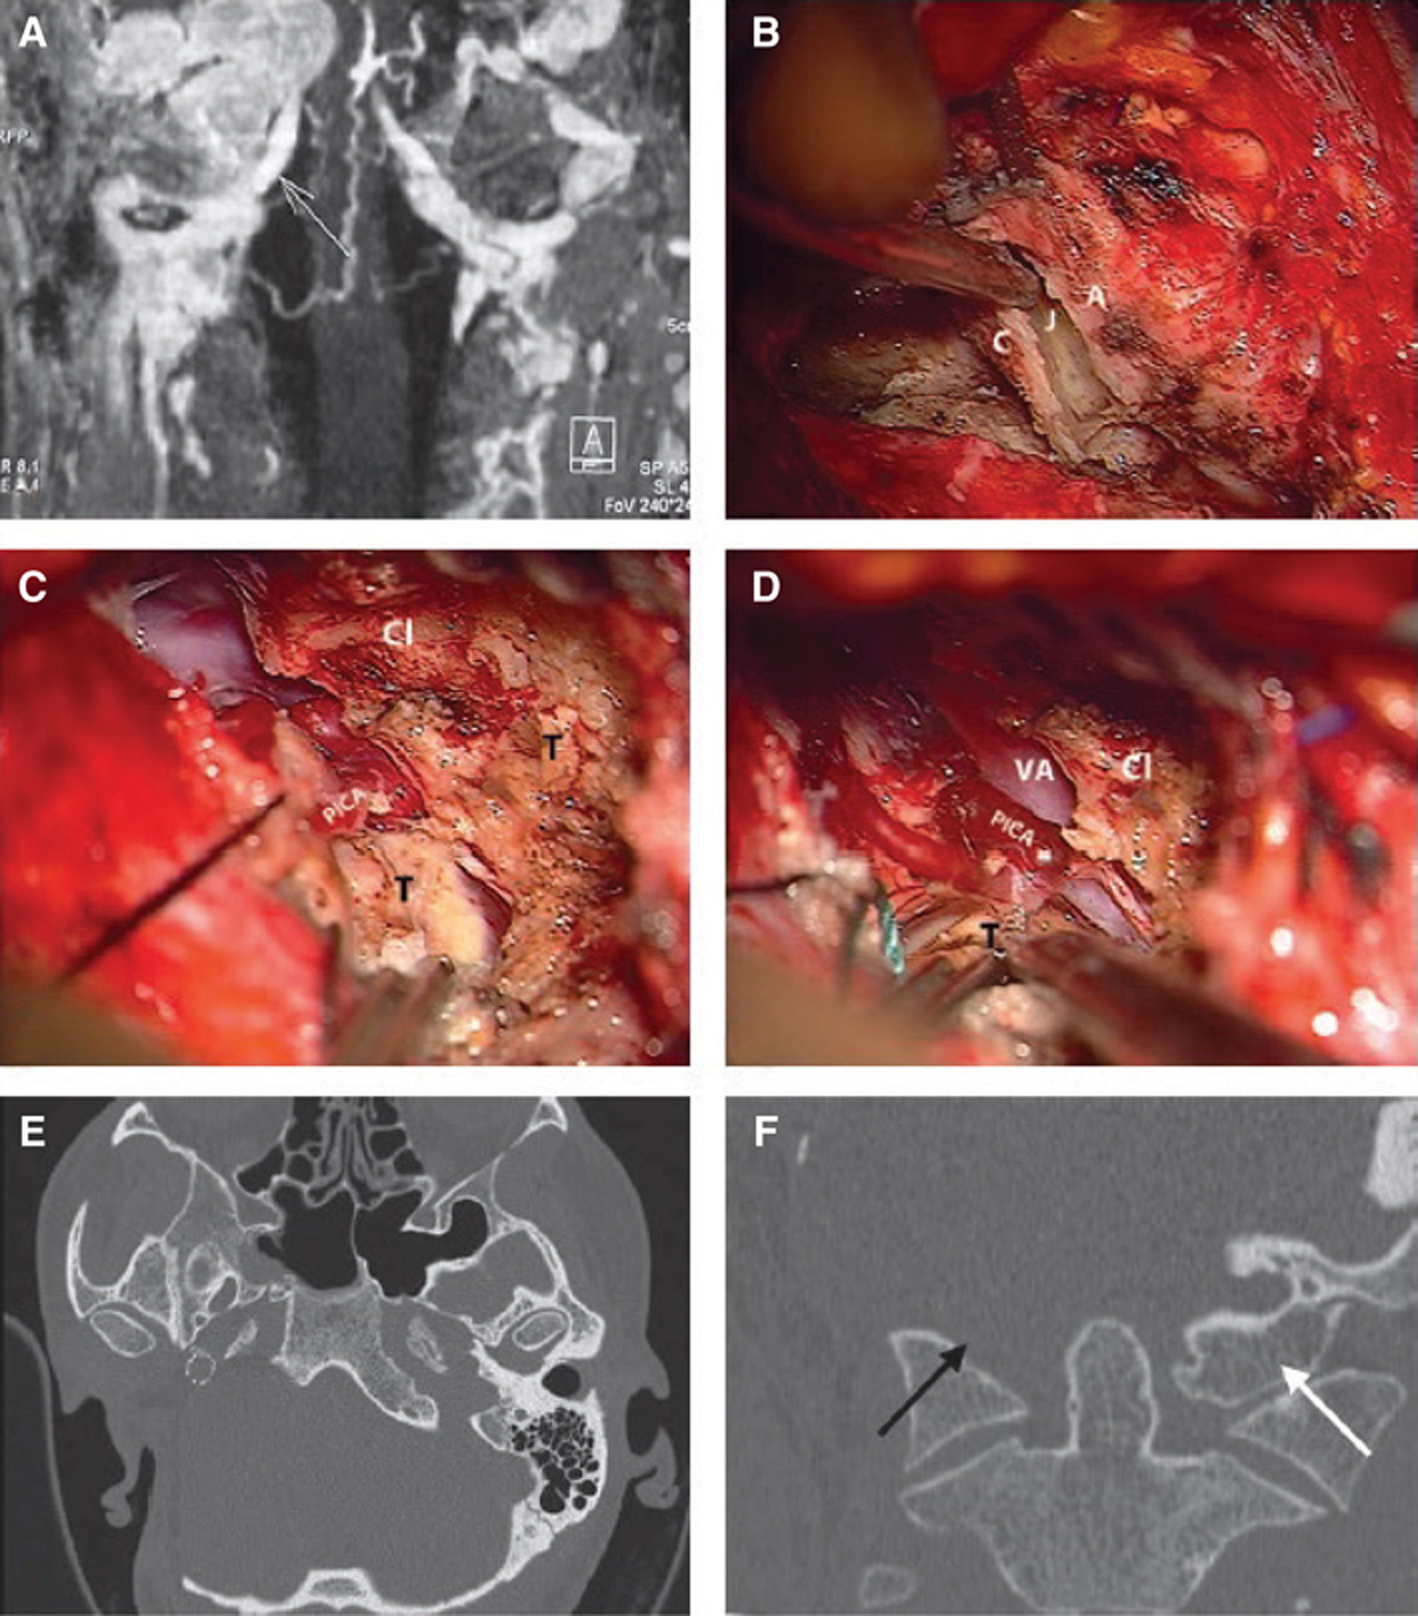

TJPs involving the VA are extremely uncommon. Only 11 cases were reported worldwide, of which eight belong to our series. We emphasized the importance of vertebral artery involvement in paragangliomas by introducing a “V” Class to the Fisch classification (2). Therefore, the vertebrobasilar system must always be included in the angiographic assessment of TJPs planned for surgery. Apart from the assessment of the VA directly, this is also useful for detecting anastomotic connections between the external carotid and the VA, which are potentially dangerous during embolization (48). The involvement of the V3 segment of the VA requires the employment of an extreme lateral extension to standard ITFA-A. As mentioned above, we prefer two-stage surgery in the case of large intradural extension (Figure 7A–F).

Fig 7

Figure 7 (A) A class C4Di2Vi tumor. MRI coronal image showing the tumor attached to the VA. (B–F) Surgical sequences of extreme lateral transcondylar approach. (B) The transverse process of the atlas (A) is drilled out and the atlanto-occipital joint (J) is removed. C = Condyle. (C) The tumor (T) is attached to the vertebral and posteroinferior cerebellar arteries infiltrating the clival (Cl) bone, which is partially drilled out. (D) The tumor is separated from the PICA. (E) CT scan. Axial view showing the stent in the ICA and the extent of bone removal. (F) CT scan coronal view showing the absence of the surgically removed occipital condyle (black arrow) compared to non-operated side (white arrow).